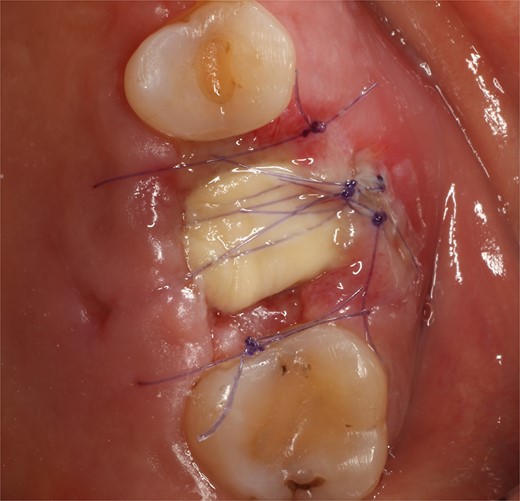

Following local anesthesia, an intrasulcural incision was made from the distal surface of the premolar, continuing through the sulcus to the mesial surface of the second molar in the vestibular and palatal surfaces. After the molar was extracted, granulation tissue was observed inside the socket that continued inside the maxillary sinus (Fig. 3); The socket was scaled, washed, and rinsed with physiological saline. The labial and palatal mucoperiosteal flaps are raised with full-thickness tunneling of the tissue, exposing the labial and palatal bone plates to allow a space for the ribose-crosslinked collagen membrane that will be used for socket closure. A 5 mm × 10 mm × 10 mm collagen sponge with hydroxyapatite and ribose was used, which was taken to the alveolus without hydration so that it absorbs as much blood as possible. It is important that the sponge has retention in the alveolus so that it does not displace within the maxillary sinus and is positioned at the same level as the remaining bone crest. A collagen membrane crosslinked with ribose was placed from buccal to palatal under the tunneled tissues (Fig. 4). A 5–0 absorbable monofilament suture was used, another layer of the collagen membrane was used in the occlusal area that was exposed, and two horizontal mattresses were sutured to give stability to the biomaterials (Fig. 5).